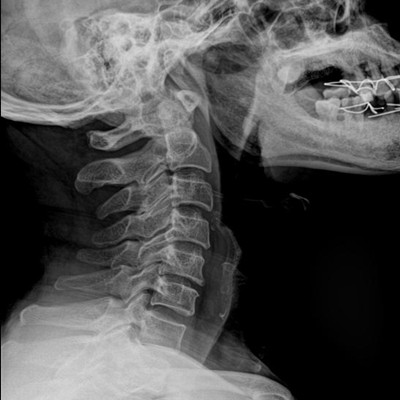

高品質(zhì)影像鏈 讓您看的更清晰 PLX8500C/D

●大尺寸非晶硅平板探測器。

●非晶硅平板探測器,采用先進的制造工藝、性能更穩(wěn)定。

●探測器可以大范圍轉(zhuǎn)動,大尺寸有效探測面積,可滿足人體多部位攝影需求。